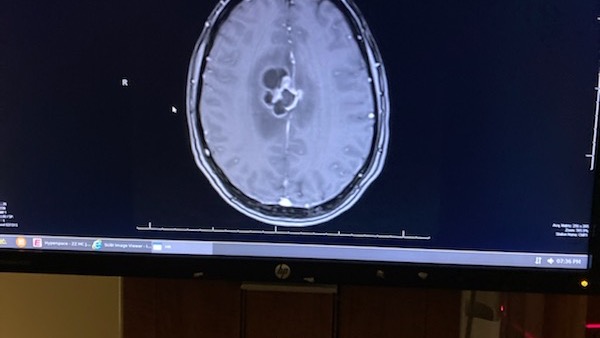

On Thursday 12/28/23 he suffered a hard hit to his head, over the next coming days he was falling a lot and showing signs of a severe concussion. The evening of 12/30 his wife Lisha took him to Atrium Health Wake Forest Baptist Hospital where they performed several scans to find that he has a Tumor in his brain.

Upon further tests and evaluation it has been determined that his tumor is more than likely glioblastoma cancer or lymphoma.

UPDATE: Chris has been diagnosed with stage 4 glioblastoma brain cancer. On Friday 1/5/24 he had as much of the tumor removed as they could and will be doing aggressive radiation and chemotherapy in the coming weeks to try to slow it down as much as they can.